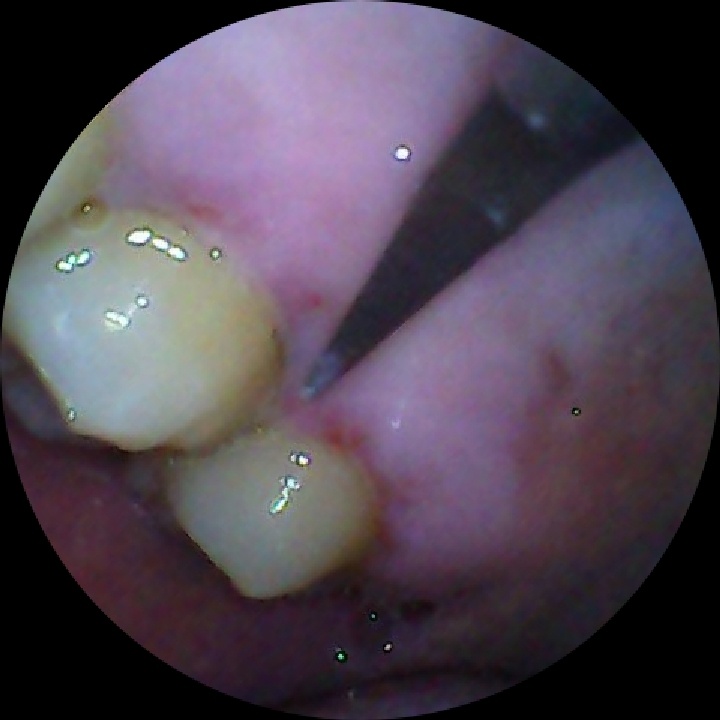

刷牙莫名其妙掉了一块牙结石。之后刷牙就有点出血。自己检查了一下,发现有点充血点,

刷牙莫名其妙掉了一块牙结石。之后刷牙就有点出血。

自己检查了一下,发现有点充血点,根本又刮出来一块牙结石。

可能跟之前用抗牙结石牙膏有关,不然应该是不会自己掉下来的。

看来要洗牙了还没洗过,先消炎几天再去。